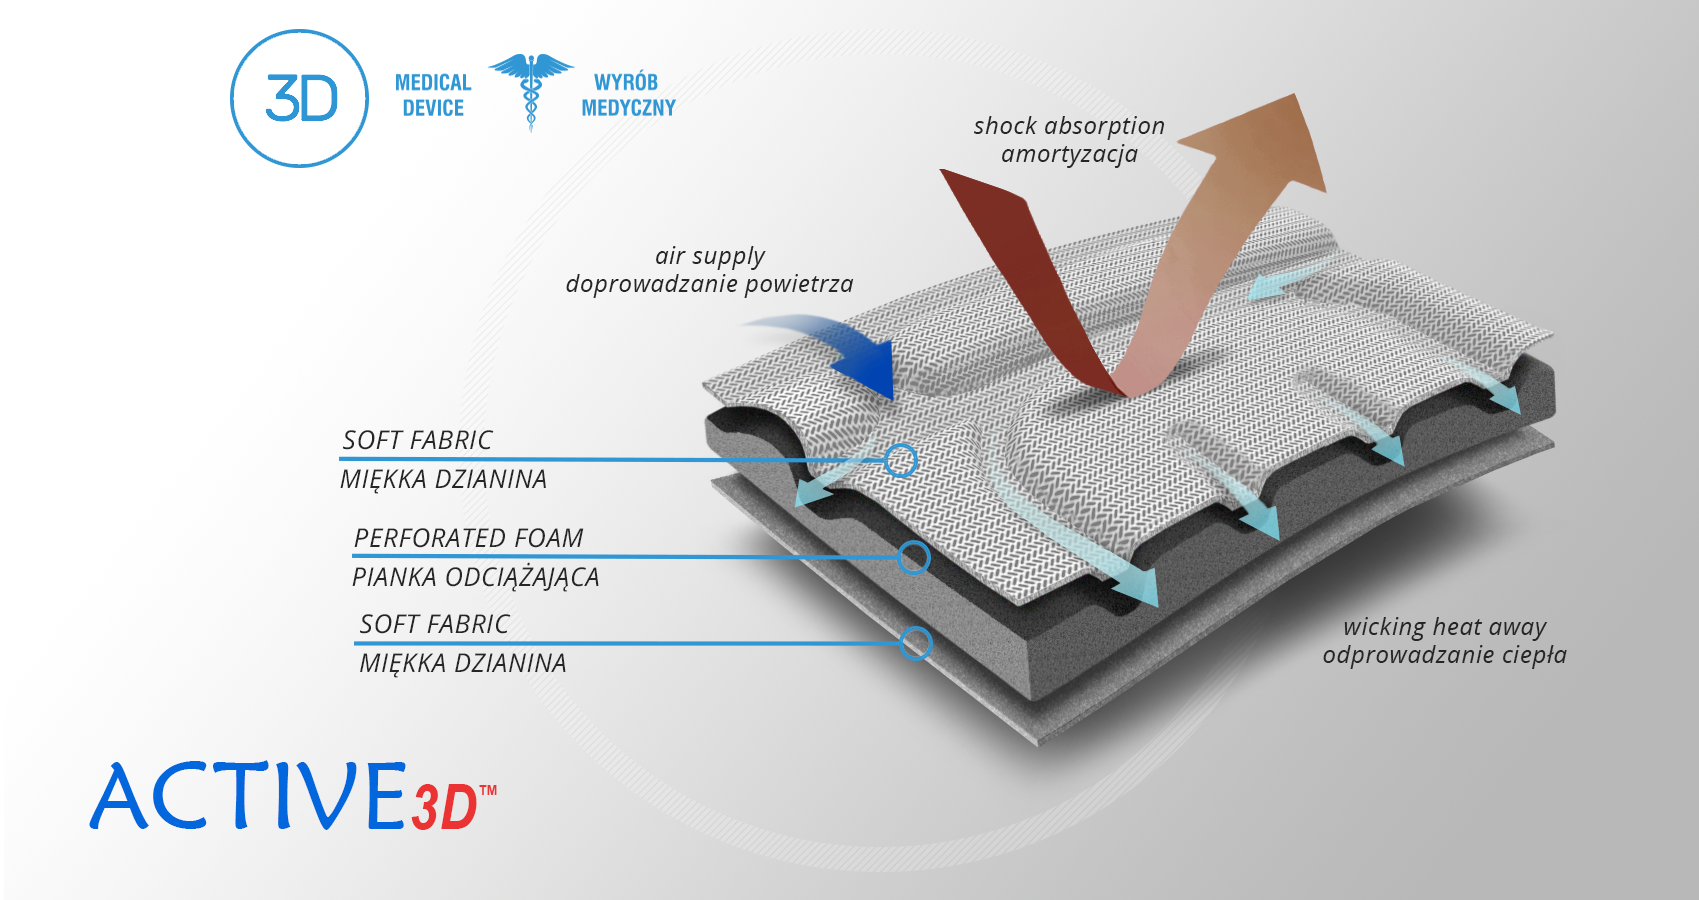

Active3D™

Active3D™ to termoformowany surowiec wykonany ze specjalnego spienionego materiału o strukturze zamknięto-komórkowej. Materiał ten doskonale odciąża od ciała takie elementy, jak szyny, stalki i fiszbiny ortopedyczne, jest wodoodporny, nie wchłania potu i jest bardzo łatwy w czyszczeniu. Ze względu na te właściwości doskonale nadaje się do konstruowania specjalistycznych ortez ortopedycznych. Surowiec może posiadać różnego typu okładziny zewnętrzne, z okładzinami o funkcjach samoszczepnych łącznie. Posiada właściwości termoformowania, dzięki czemu można mu nadać kształty i funkcjonalność niezbędną do wykonania danego typu ortezy.